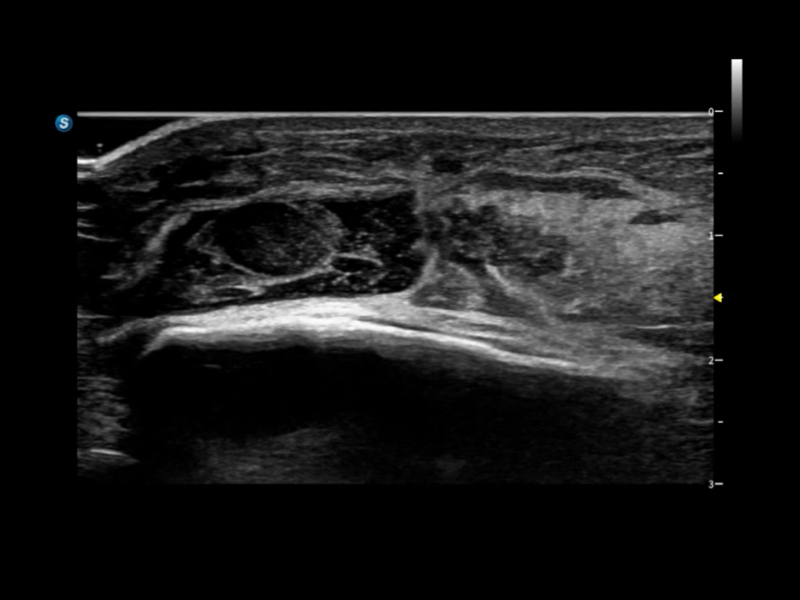

通過創(chuàng)新的Matrix E自適應(yīng)濾波算法,能有效濾除軟組織和噪聲信號(hào),最大限度保留超低速微細(xì)血流的信號(hào);結(jié)合超長(zhǎng)時(shí)間域算法,極大提升細(xì)微血流的敏感性和空間分辨率,更真實(shí)的反應(yīng)組織、包塊的血流灌注情況。